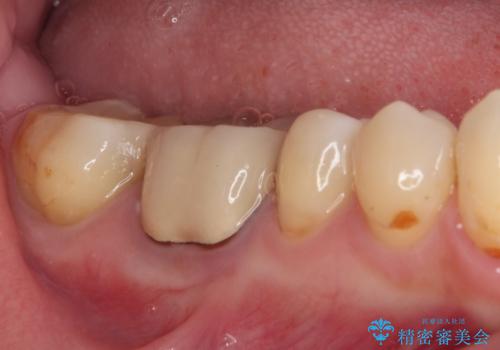

精度の高いセラミックインレーによる修復治療を行うこととしました。

セラミックインレー装着後はフロスの引っかかるストレスから解放され、患者様には大変満足していただきました。